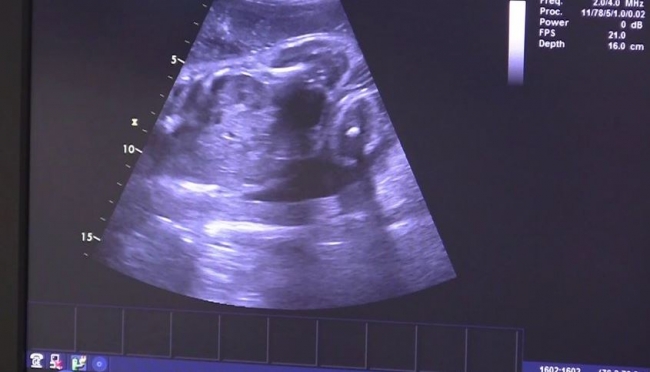

Nisan ayında hastaneye kaldırılan Eva’nın karnındaki fetüs, yaklaşık 300 gram ağırlığındaydı. Brno Üniversite Hastanesindeki doktorlar, hastanede makinelere bağlı olarak 3,5 ay geçiren Eva’yı ameliyathaneye aldı.

21 Nisan günü Vojtech, eve geldiğinde eşi Eva’yı bilincini kaybetmiş şekilde buldu. Helikopterle hastaneye kaldırılan Eva, bilinçsiz bir durumda, dolaşımı sabit tutularak ve vücut sıcaklığını azaltılarak, Resüsitasyon ve Yoğun Tıp Bölümüne alındı. Karnındaki fetüsün kalbinin de düzenli bir şekilde attığı tespit edildi.